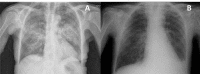

Figure 1

(A) Chest radiographs with diffuse bilateral infiltration; (B) Chest radiographs 15 days post-treatment, with marked improvement of the bilateral infiltrates.